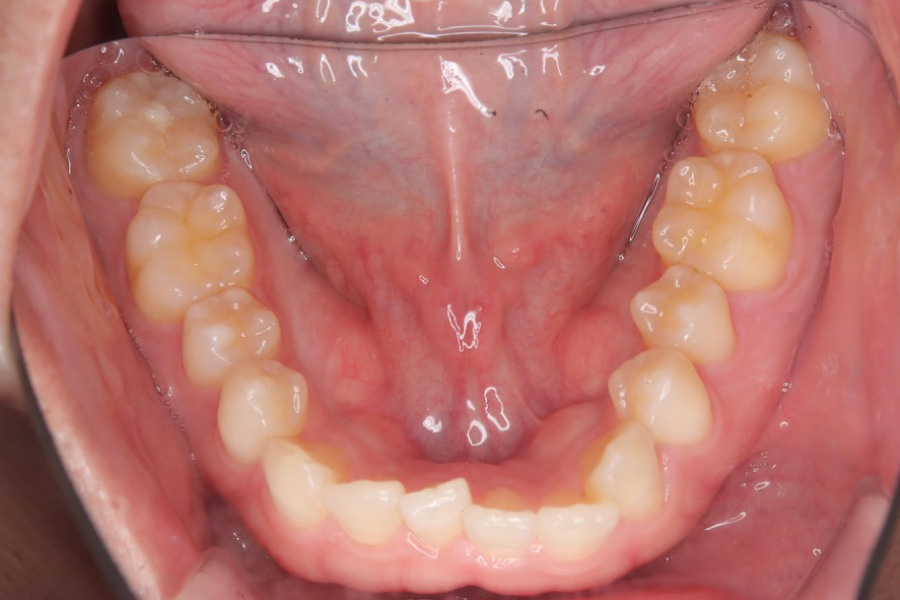

治療前

主訴 歯のガタつき

治療内容 インビザライン矯正

非抜歯